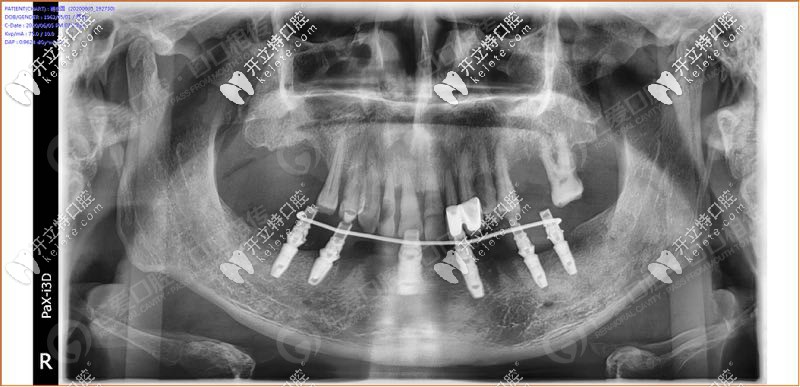

經(jīng)過我院種植醫(yī)生面診,拍片檢查發(fā)現(xiàn),31、32 、33、 34顆牙松動(3度),43顆牙也松動了, 44、45多年前做了烤瓷牙修復(fù),其余牙缺失。

具體設(shè)計方案:拔除下半口松動牙后,在33、34、36、43、44、46牙窩采用種植導(dǎo)板植入性價比高的登騰種植體,當(dāng)天帶上牙冠,實(shí)現(xiàn)“當(dāng)天種牙,當(dāng)天用”。

手術(shù)時,我院采用的種植導(dǎo)板技術(shù),術(shù)前設(shè)計,種植體植入方向、位置、角度、深度等一目了然,導(dǎo)板輔助將種植植入到理想位置,有效避開神經(jīng)、血管等危險區(qū)域,同時也大大縮短手術(shù)時間,在拔牙窩即拔即種,沒有切口或切小口,愈合快。

順利植入6顆種植體后,把過渡性臨時假牙固定到下頜的種植體上實(shí)現(xiàn)了當(dāng)天種牙,當(dāng)天用的即刻負(fù)重種植牙。